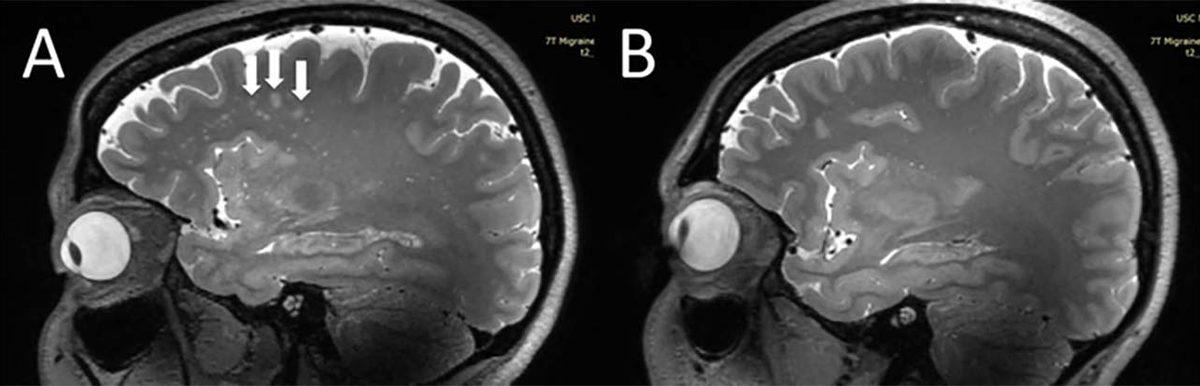

Migrene sahip kişilerin beyninde gözlemlenen değişiklik:

- A: Migenli kişiye ait MRI, B: Migrensiz kişiye ait MRI

Güney Kaliforniya Üniversitesi’nden bilim insanları, migrene sahip kişilerin beynindeki değişikliği ilk kez tespit etti. Kronik ve aurasız epizodik migrenli kişilerde, ‘centrum semiovale’ adı verilen beyin bölgesinin mikroskobik boyuttaki perivasküler boşluklarının büyüdüğü gözlemlendi.

Perivasküler boşluk olarak tanımlanan alan, beyindeki kan damarlarını çevreleyen sıvı boşluklardan oluşuyor. Bu boşluklar, özellikle kan-beyin bariyerindeki anormallikler ve iltihap gibi durumlardan etkileniyor.